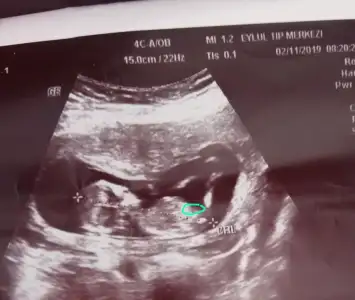

Bana senin bebeğinin nubu burası gibi geldi

Anladım canım hangi çıkıntıyı dediğini diğer sayfalarda da gördüm

Bence orası nubu değil çünkü hemen yanındaki parlaklık bebeğin elinin parlaklığı

Canım asıl senin işaretlediğin yer kenarda duruyor o nubu değil, inşallah haber ederim haftaya☺bugün o işaretlediğim yer biraz daha büyüktü ve bayağı net belliydi

Canım bence yakınlaştırıp bak

Bi de matematiksel olarak bebeğin duruş açısına göre oranın nub olması biraz zor gibi